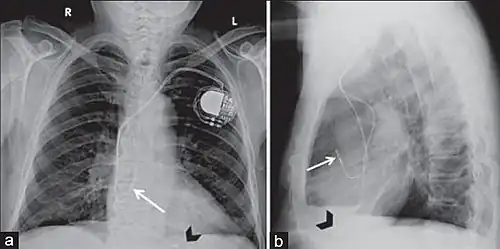

Posteroanterior and lateral chest radiographs of a pacemaker with normally located leads in the right atrium (white arrow) and right ventricle (black arrowhead), respectively